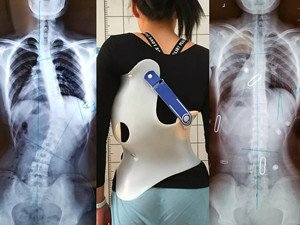

在青少年快速發(fā)育期內(nèi),身體長得越快,脊柱側彎的進展就越快。矯形支具通過長時的反向矯正力將脊柱維持在一個矯正的狀態(tài);然而由于長時間地佩戴支具會導致肌肉萎縮,當支具摘除,脊柱側彎回彈,且患者無法形成成自我矯正力,呼吸功能亦無法得到改善。最好是在穿戴支具的同時,配合體操訓練,通過一系列矯正動作以及呼吸訓練,平衡肌力,兩者結合不但可以穩(wěn)定脊柱,且能增加改善機會。